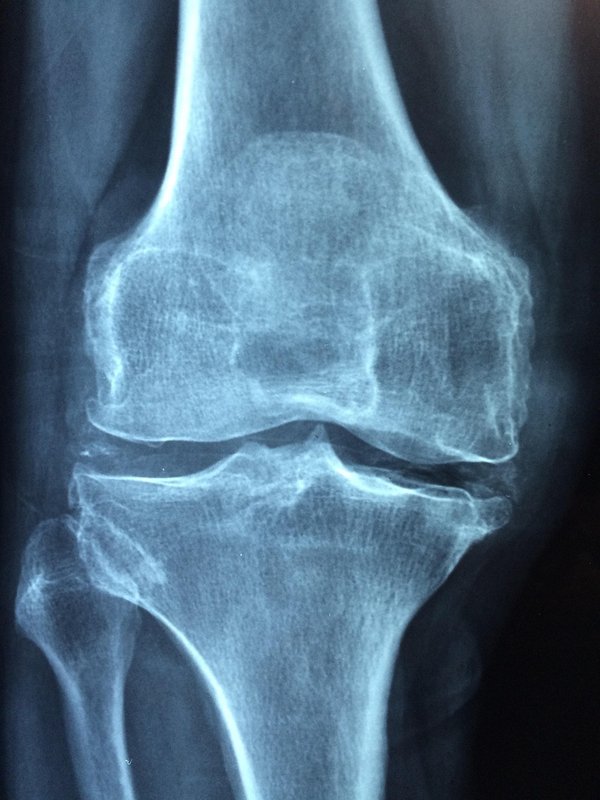

L'arthrose provoque douleur et raideur, affectant la qualité de vie de millions de personnes. Comprendre ses causes et les traitements adaptés permet d'atténuer les symptômes et de préserver la mobili...